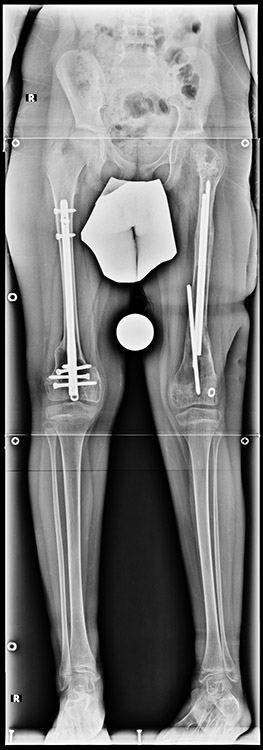

3. POSTTRAUMATIC LOWER LIMB SHORTNESS (MALUNION)

This type of shortness occurs after a fracture heals in a shortened position. Most cases are seen in adults and can be treated with one lengthening operation. Additional deformities can be corrected simultaneously. Most of these cases can be treated with lengthening over nail or just corrections and intramedullary nailing.